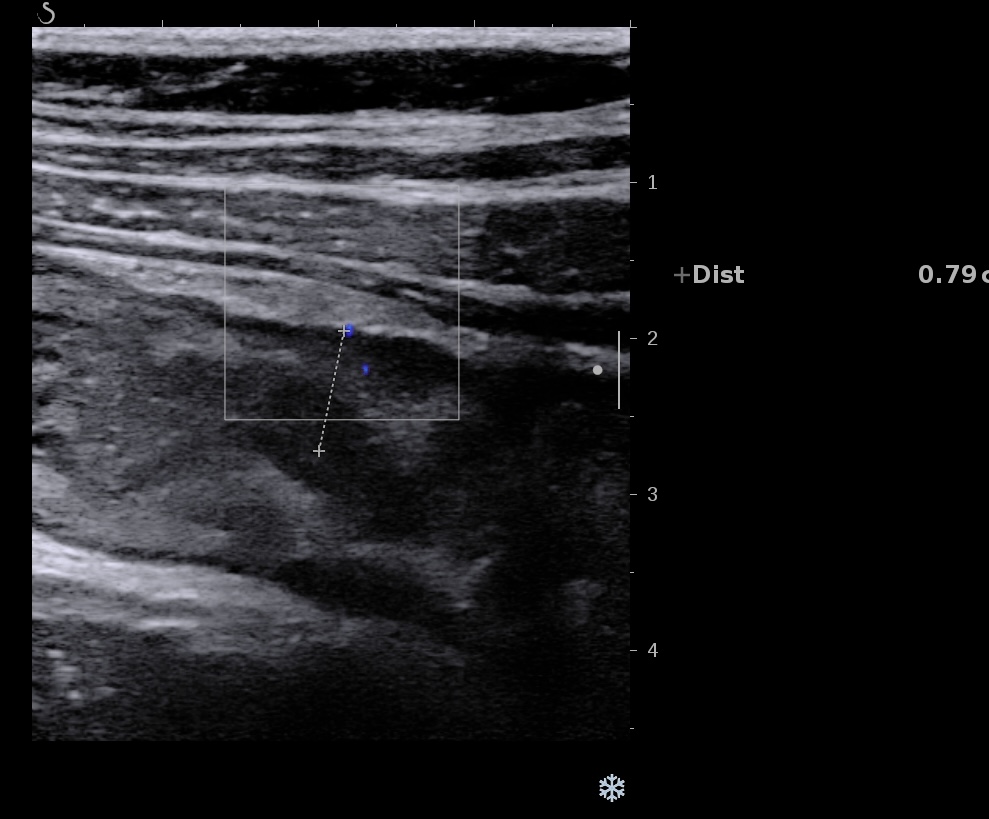

Iléïte aigue inflammation de la muqueuse très hypoéchogène, la sous muqueuse et la musculeuse sont intactes

Iléïte aiguë infectieuse